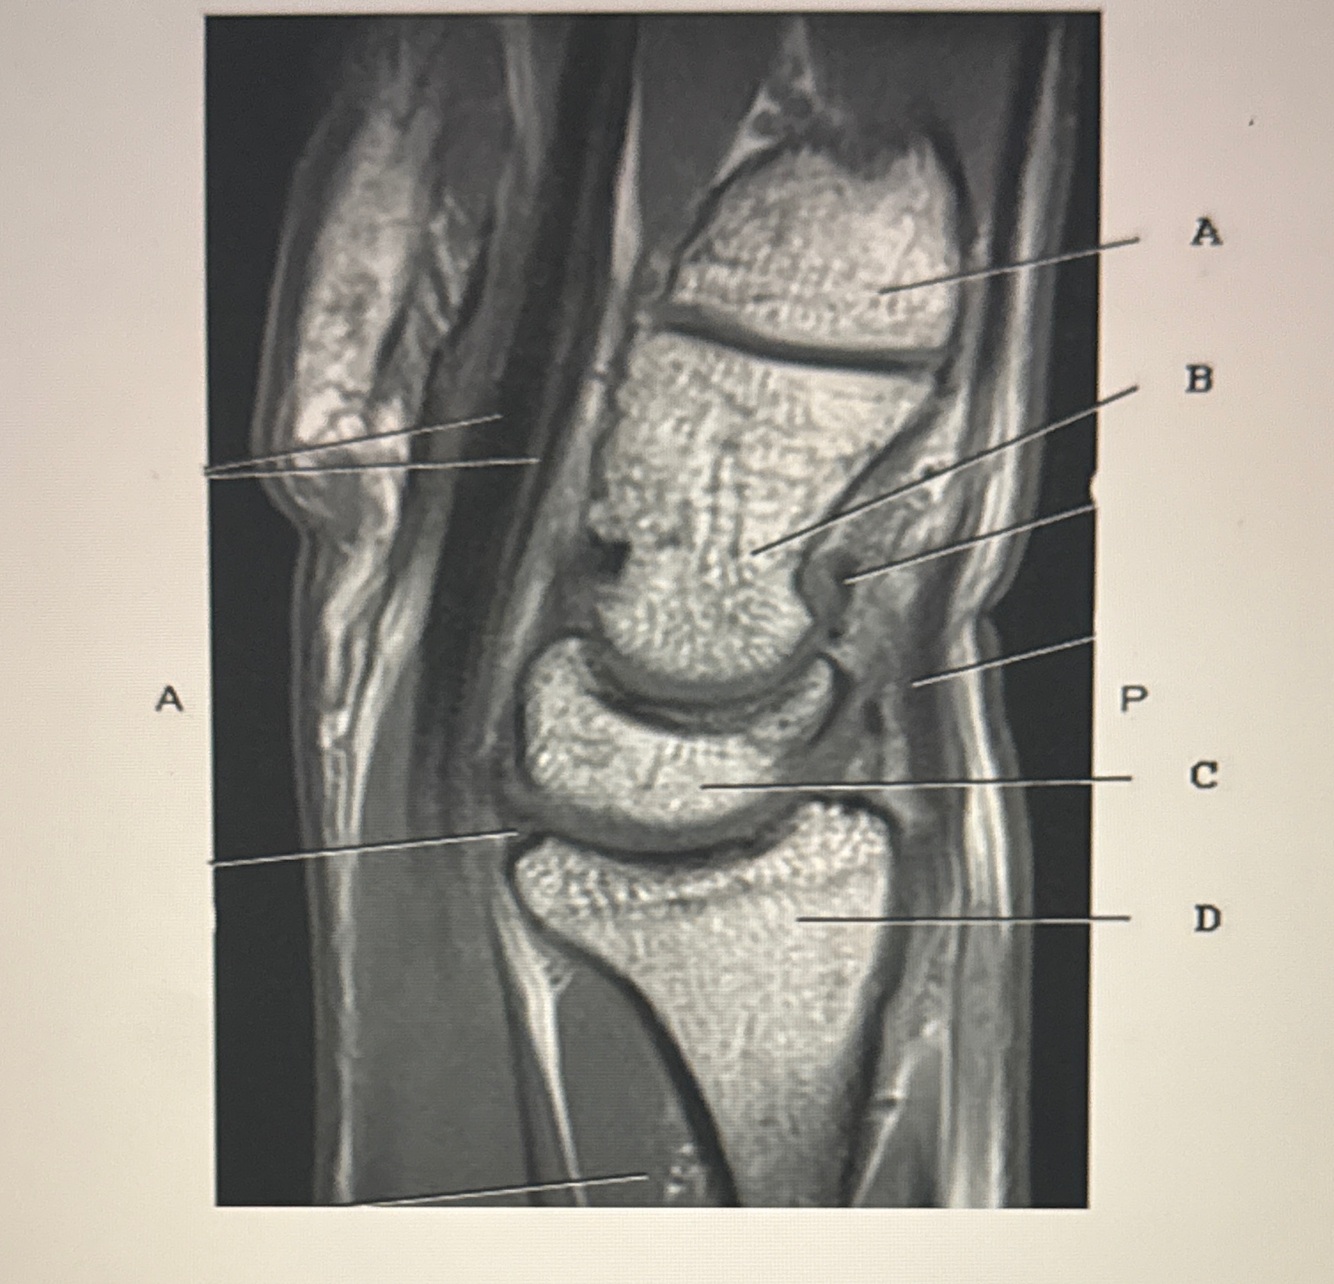

Q

1. Which line points to the radius?

2. Which line points to the lunate?

A

1. D

2. C